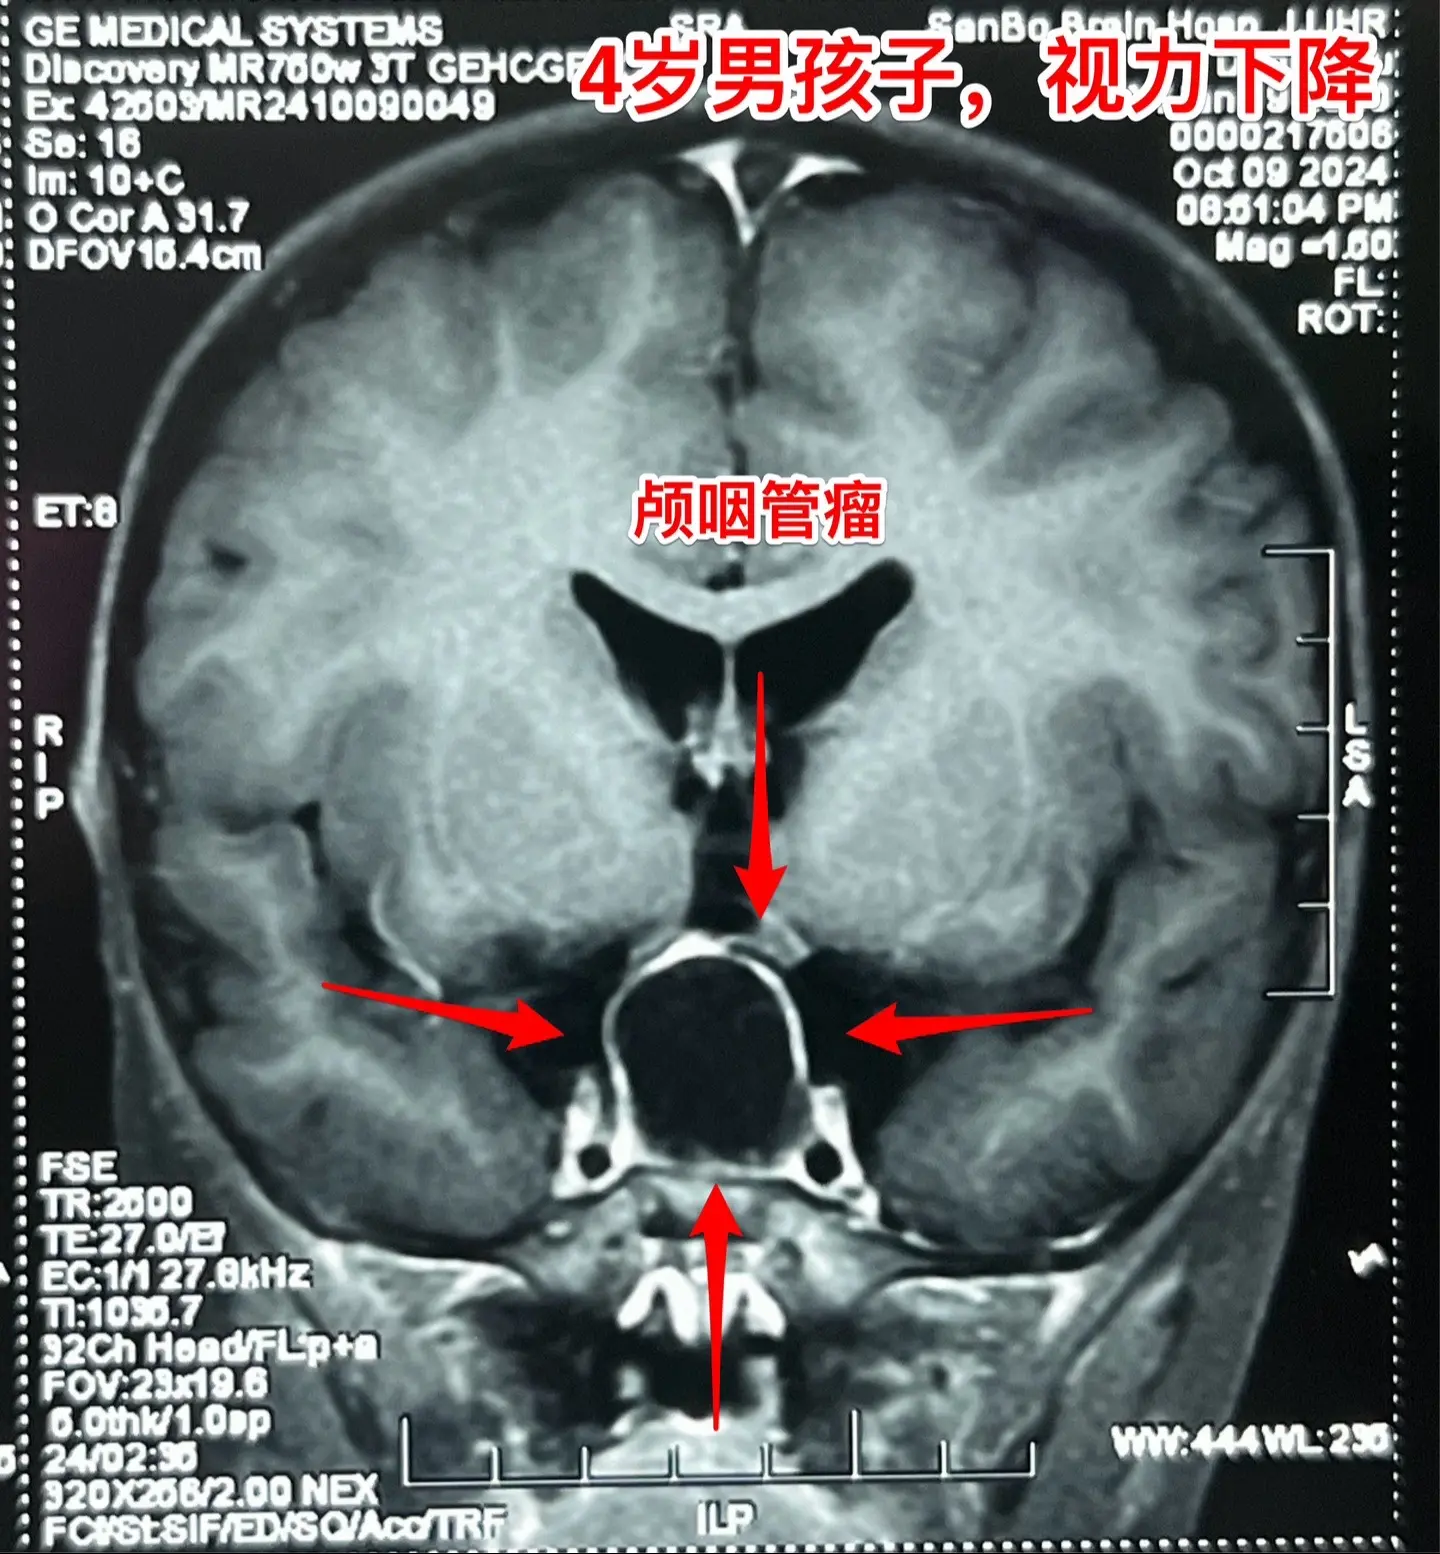

一天完成两个颅咽管瘤手术几乎成了常态。今天的两个颅咽管瘤手术,强度很大哦! 1,4岁男孩子,视力下降。典型的造釉细胞型颅咽管瘤,属于鞍隔下颅咽管瘤。开颅手术将颅咽管瘤完全切除,垂体大部分保留,垂体柄保留,下丘脑保护完好。这样的结果我们很满意! 2,35岁女性,经鼻手术后颅咽管瘤复发,视力下降。是乳头型颅咽管瘤。肿瘤与视交叉粘连很紧,手术分离难度大,最终得到完全切除。